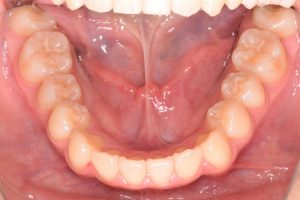

1期治療開始時(2024年3月)

2期治療開始時(2024年11月)

保定開始時(2025年1月)の写真です。

正面

上あご

下あご